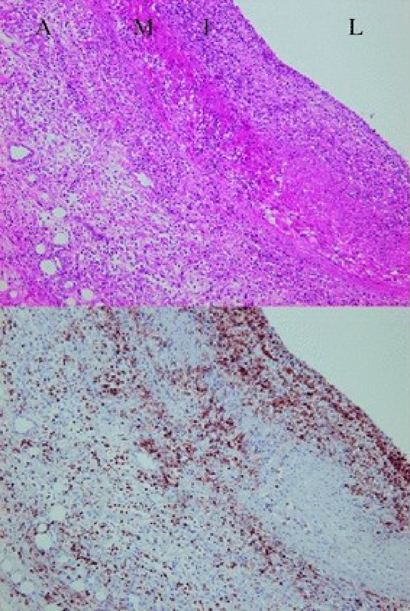

Fig. 2 川崎病急性期血管炎の病理組織.管腔側と外膜側の両方から炎症細胞が血管壁に侵入し汎血管炎に至る

発症後10日目,上段:HE染色,下段:anti-leukocyte common antigenによる免疫染色像.L: 血管腔,I: 内膜,M: 中膜,A: 外膜.(文献15より引用)